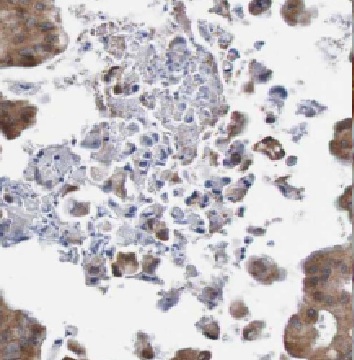

| 验证图片 | Immunohistochemistry of paraffin-embedded human ovary tumor tissue slide using FNab03813(HE4 Antibody) at dilution of 1:50 |

| 建议稀释比例 | IHC: 1:20-1:200 |